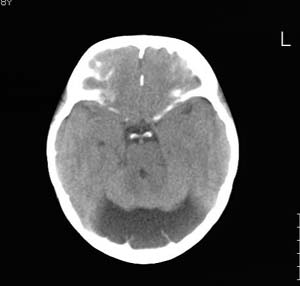

以下是引用wxy7406在2006-12-5 21:02:00的发言:[br]后颅窝囊性低密度灶,双侧小脑半球缩小,蚓部几乎缺失,考虑dandy-walker畸形,建议mri明确。

以下是引用阿圣在2006-12-5 20:55:00的发言:[br]后颅窝囊性低密度灶,双侧小脑半球缩小,蚓部几乎缺失,考虑dandy-walker畸形,建议mri明确